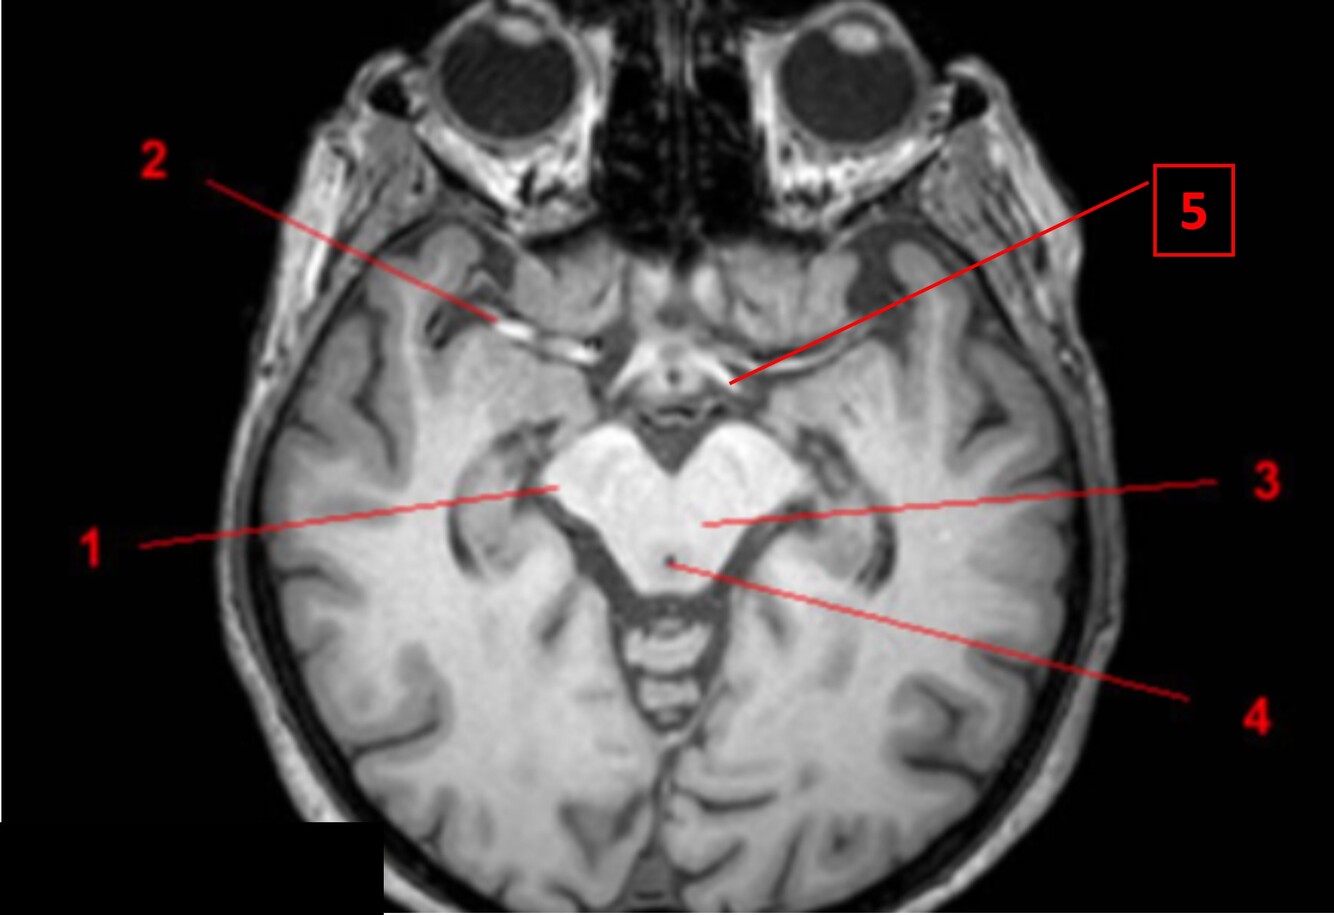

9

Q

Label 1-5

A

1. Rt cerebral peduncle of midbrain

2. Rt middle cerebral artery

3. Midbrain

4. Cerebral aqueduct

5. Lt optic tract